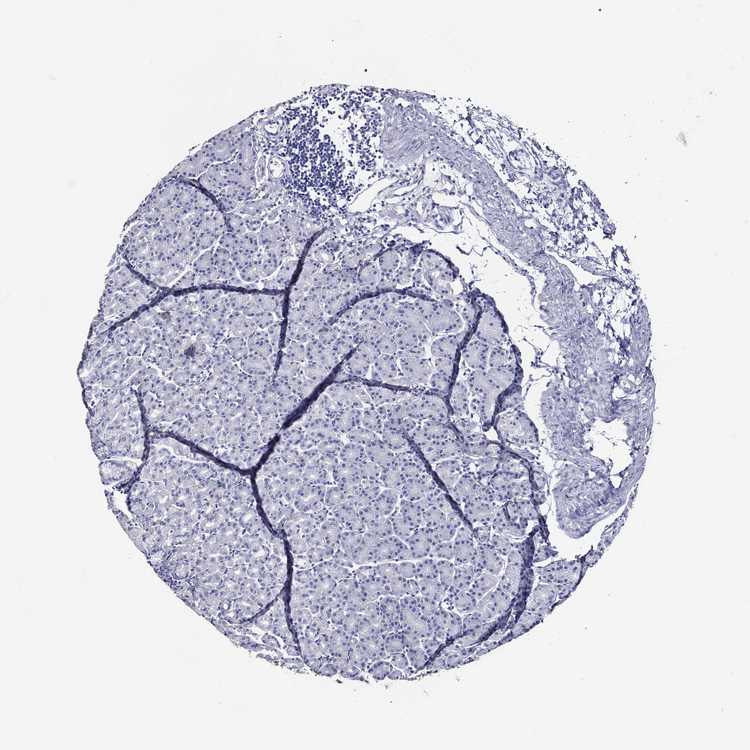

STOMACH 1 - Antibody stainingi

Antibody staining in the annotated cell types in the current human tissue is reported as not detected, low, medium, or high, based on conventional immunohistochemistry profiling in selected tissues. This score is based on the combination of the staining intensity and fraction of stained cells.

Each image is clickable and will lead to virtual microscopy that enables deeper exploration of all samples and also displays staining intensity scores, fraction scores and subcellular localization as well as patient and tissue information for each sample.

Antibody HPA000288Antibody CAB026174Antibody CAB026213Antibody CAB080024Antibody CAB080025Antibody CAB080027Antibody CAB080028

Glandular cells Not detectedNot detectedNot detectedNot detectedLowNot detectedLow